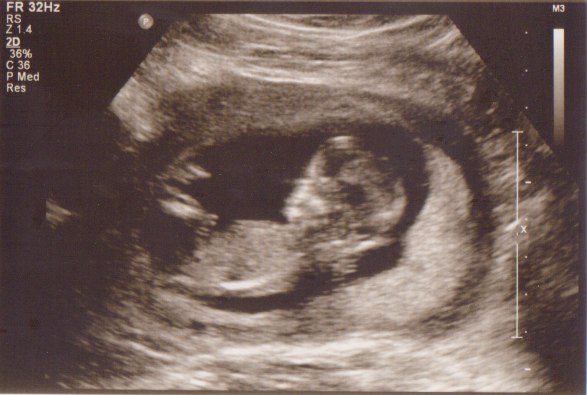

Ja, det kan jeg godt se, bliver spændende, hvad de svarer... Husk og fortæl, hvis du skal til scanning